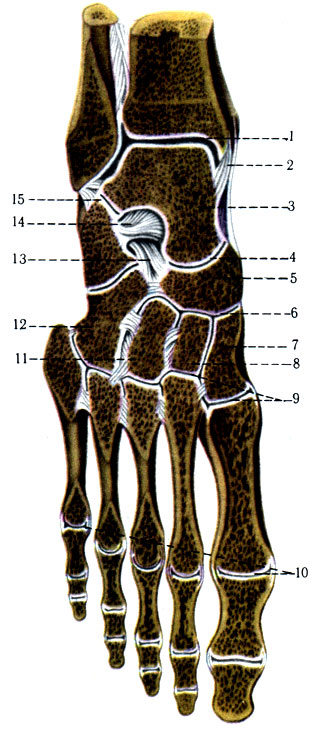

Анатомия суставов Шапарова и Лисфранка: фото и информация